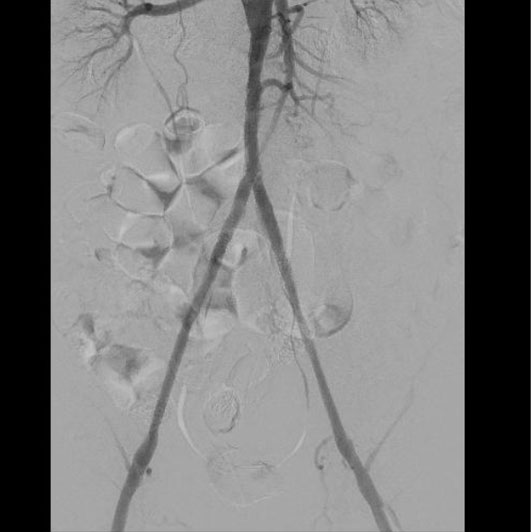

Пациенту была выполнена высокотехнологичная миниинвазивная эндоваскулярная операция – баллонная ангиопластика и стентирование брюшного отдела аорты, левой и правой подвздошных артерий, с хорошим результатом, с полным восстановлением прямого кровотока на всем протяжении обеих нижних конечностей. Данная операция миниинвазиваная, длилась 2.5 часа, была выполнена через 2 маленьких прокола в руке и ноге под местной анестезией и является альтернативой большой и долгой полостной операции, с разрезом брюшной полости под общим наркозом, которые чаще всего выполняются при таком сложном поражении.